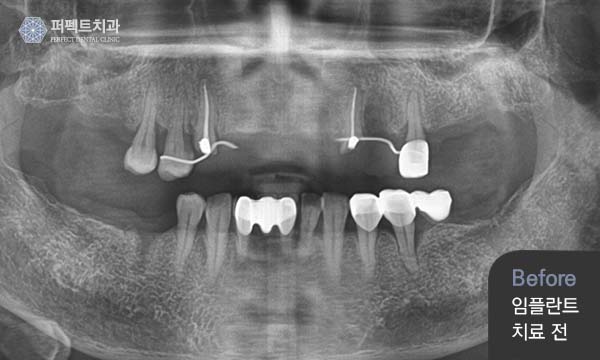

다양한 케이스들의 임플란트 수술과

퍼펙트치과는 다양한 케이스와

풍부한 임플란트 식립경험으로 임플란트를 찾는 환자분들에게

신뢰를 주고 만족하실 수 있는 치료를 하고 있습니다.